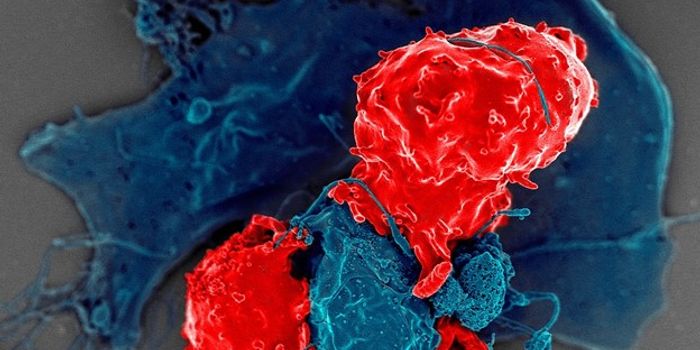

MAR 21, 2024CancerLymphocytes, the white blood cells circulating in the body, provide many vital functions to support the immune response. ...